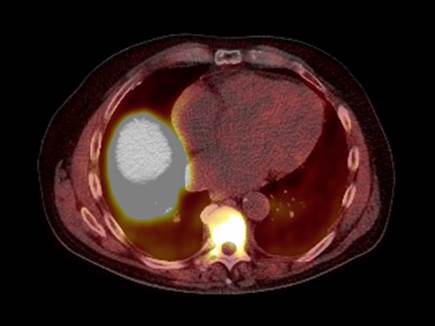

Palliative radiotherapy is used to relieve our patients of pain or other distressing symptoms of their cancer and to improve their quality of life. It has traditionally been associated with the use of simple planning and delivery techniques but there is now increasing interest in the use of the latest treatment techniques such as Intensity-Modulated Radiation Therapy (IMRT) and Stereotactic ablative radiotherapy (SABR) to provide more effective and durable control and reduce toxicity. Alongside these developments, there has also been a change to a more multidisciplinary approach in the management of palliative cancer care with consultant therapeutic radiographers and nurses taking an increasingly active role in the planning of palliative radiotherapy.